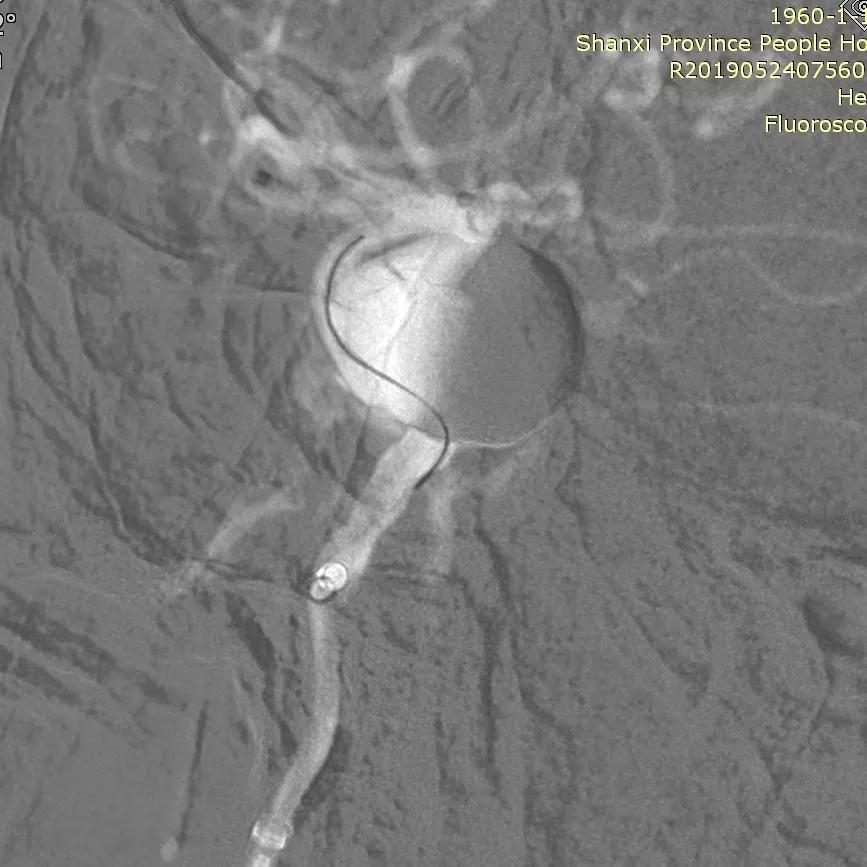

全脑血管造影可见右侧颈内动脉海绵窦巨大动脉瘤,瘤体最大径:14.72mm,瘤颈宽:9.12mm。

Synchro 14导丝顺利送支架导管入右侧中动脉下干远端,尾部连接Y阀1个,压力带1个;经支架导管,置入Tubridge® 4.5×35mm,定位良好,顺利释放。

复查造影显示,动脉瘤内造影剂滞留明显,各血管及分支通畅,流速正常。手术结束。